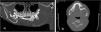

The evaluation was completed with a CT scan that confirmed the presence of a large cystic lesion, with no involvement of soft tissues, suggestive of a calcifying odontogenic cyst (COC) (Fig. 3).

Computed tomography scan, bone window. (A) Curved planar reconstruction: large multilocular cystic lesion located in the located in the body and ramus of the left mandible with thin inner septae and subtle scalloped outline of the inner cortical bone. (B) Axial plane: hypodense content without involvement of soft tissues; displacement of teeth.